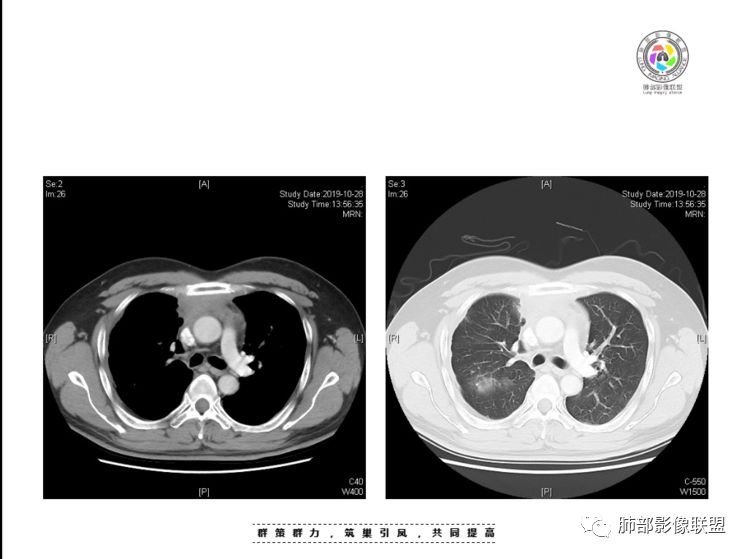

肺内结节,近端支气管堵塞狭窄

整体边缘收缩,部分膨隆

炎性要考虑,但恶性不能排除

1、右肺内病灶,病灶呈结节样,边缘欠规则,局部膨隆,叶间裂胸膜牵拉凹陷,再看相应支气管腔堵塞截断,临床资料胸水中查到癌细胞,均提示病灶倾向恶性,腺癌的病理意见与之相吻合。